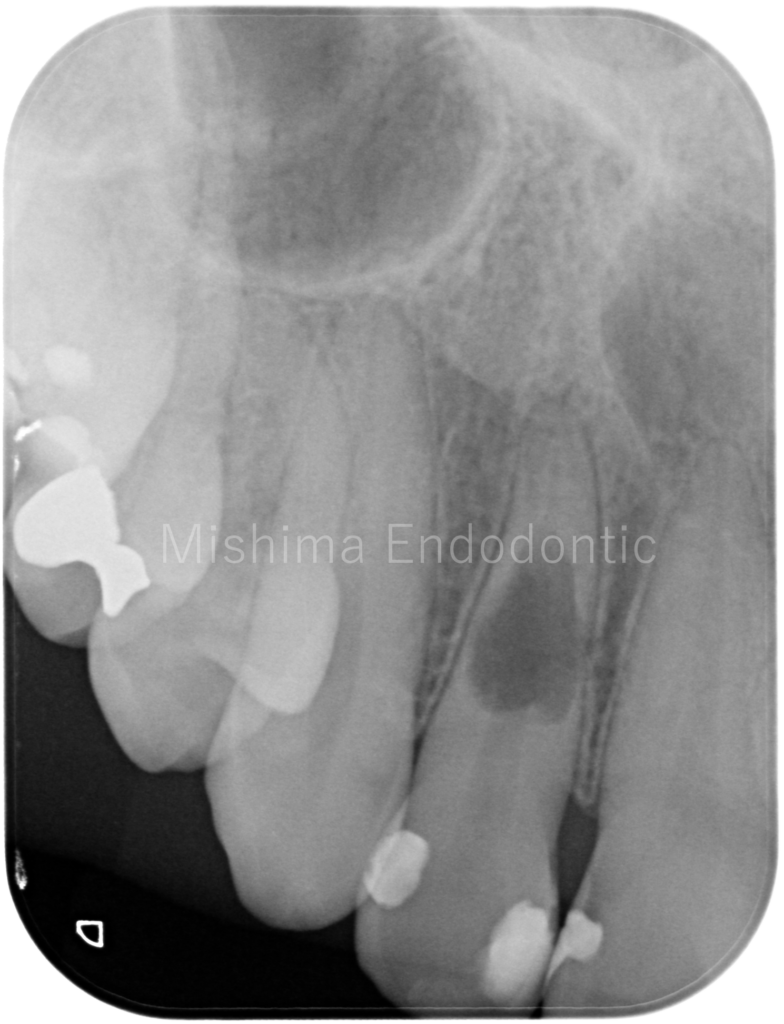

Before

| 治療内容 | 歯髄診査により生活反応は認めない。X線にて内部炎症性吸収と診断。根管内を精査したところ、吸収部より根尖の歯髄は生活していた。根管治療を行い、バイオセラミックのパテにて充填。術後、症状、以上所見は認めず経過は良好。 |

術前